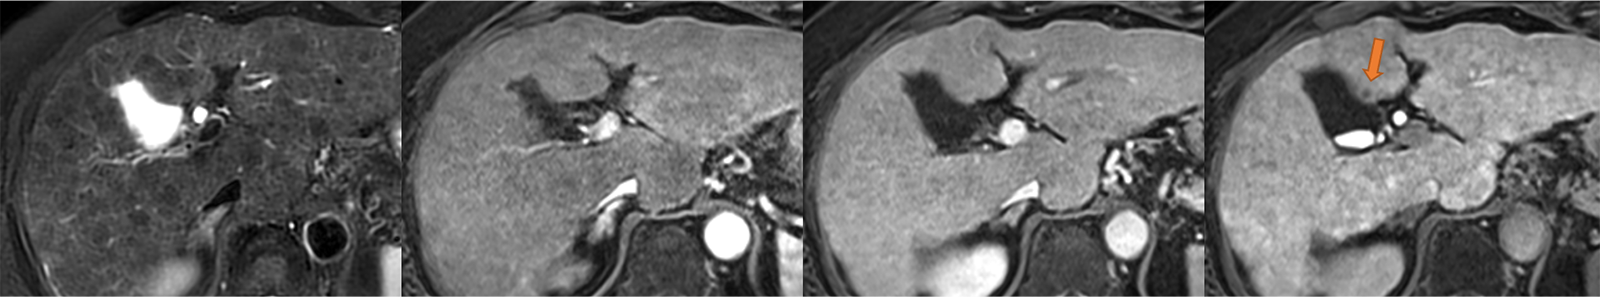

図1.初診時EOB-MRI画像(左から脂肪抑制T2強調画像、動脈相、門脈相、肝細胞相)

肝細胞相で肝S4に小径の低信号結節が見られる(矢印)。早期濃染やwashoutは見られず、T2WIでの所見も明瞭ではない。背景には再生結節が散見される。